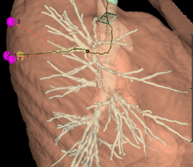

Reconstructions 3D

De quoi s’agit-il ?

Nous reconstruisons l’anatomie du patient en 3 dimensions grâce à un scanner thoracique (en utilisant le logiciel Synapse 3D) avant l’opération afin de la préparer car chaque patient est unique et chaque anatomie est différente.

A quoi ça sert ?

Les reconstructions 3D permettent au chirurgien de :

- diminuer la durée de l’intervention chirurgicale grâce à un gain de temps de dissection

- planifier le déroulé de l’intervention chirurgicale, c’est-à-dire , prévoir les étapes de dissection de l’organe

- réaliser des interventions plus complexes qu’auparavant grâce à une meilleure précision de la connaissance de l’anatomie du patient qui est soigné

- diminuer le risque d’erreur anatomique pendant l’opération quand les patients ont une anatomie inhabituelle

- diminuer le risque d’accident hémorragique lors de l’intervention

- améliorer les marges de résection de sécurité d’une tumeur en augmentant ainsi la qualité oncologique du geste